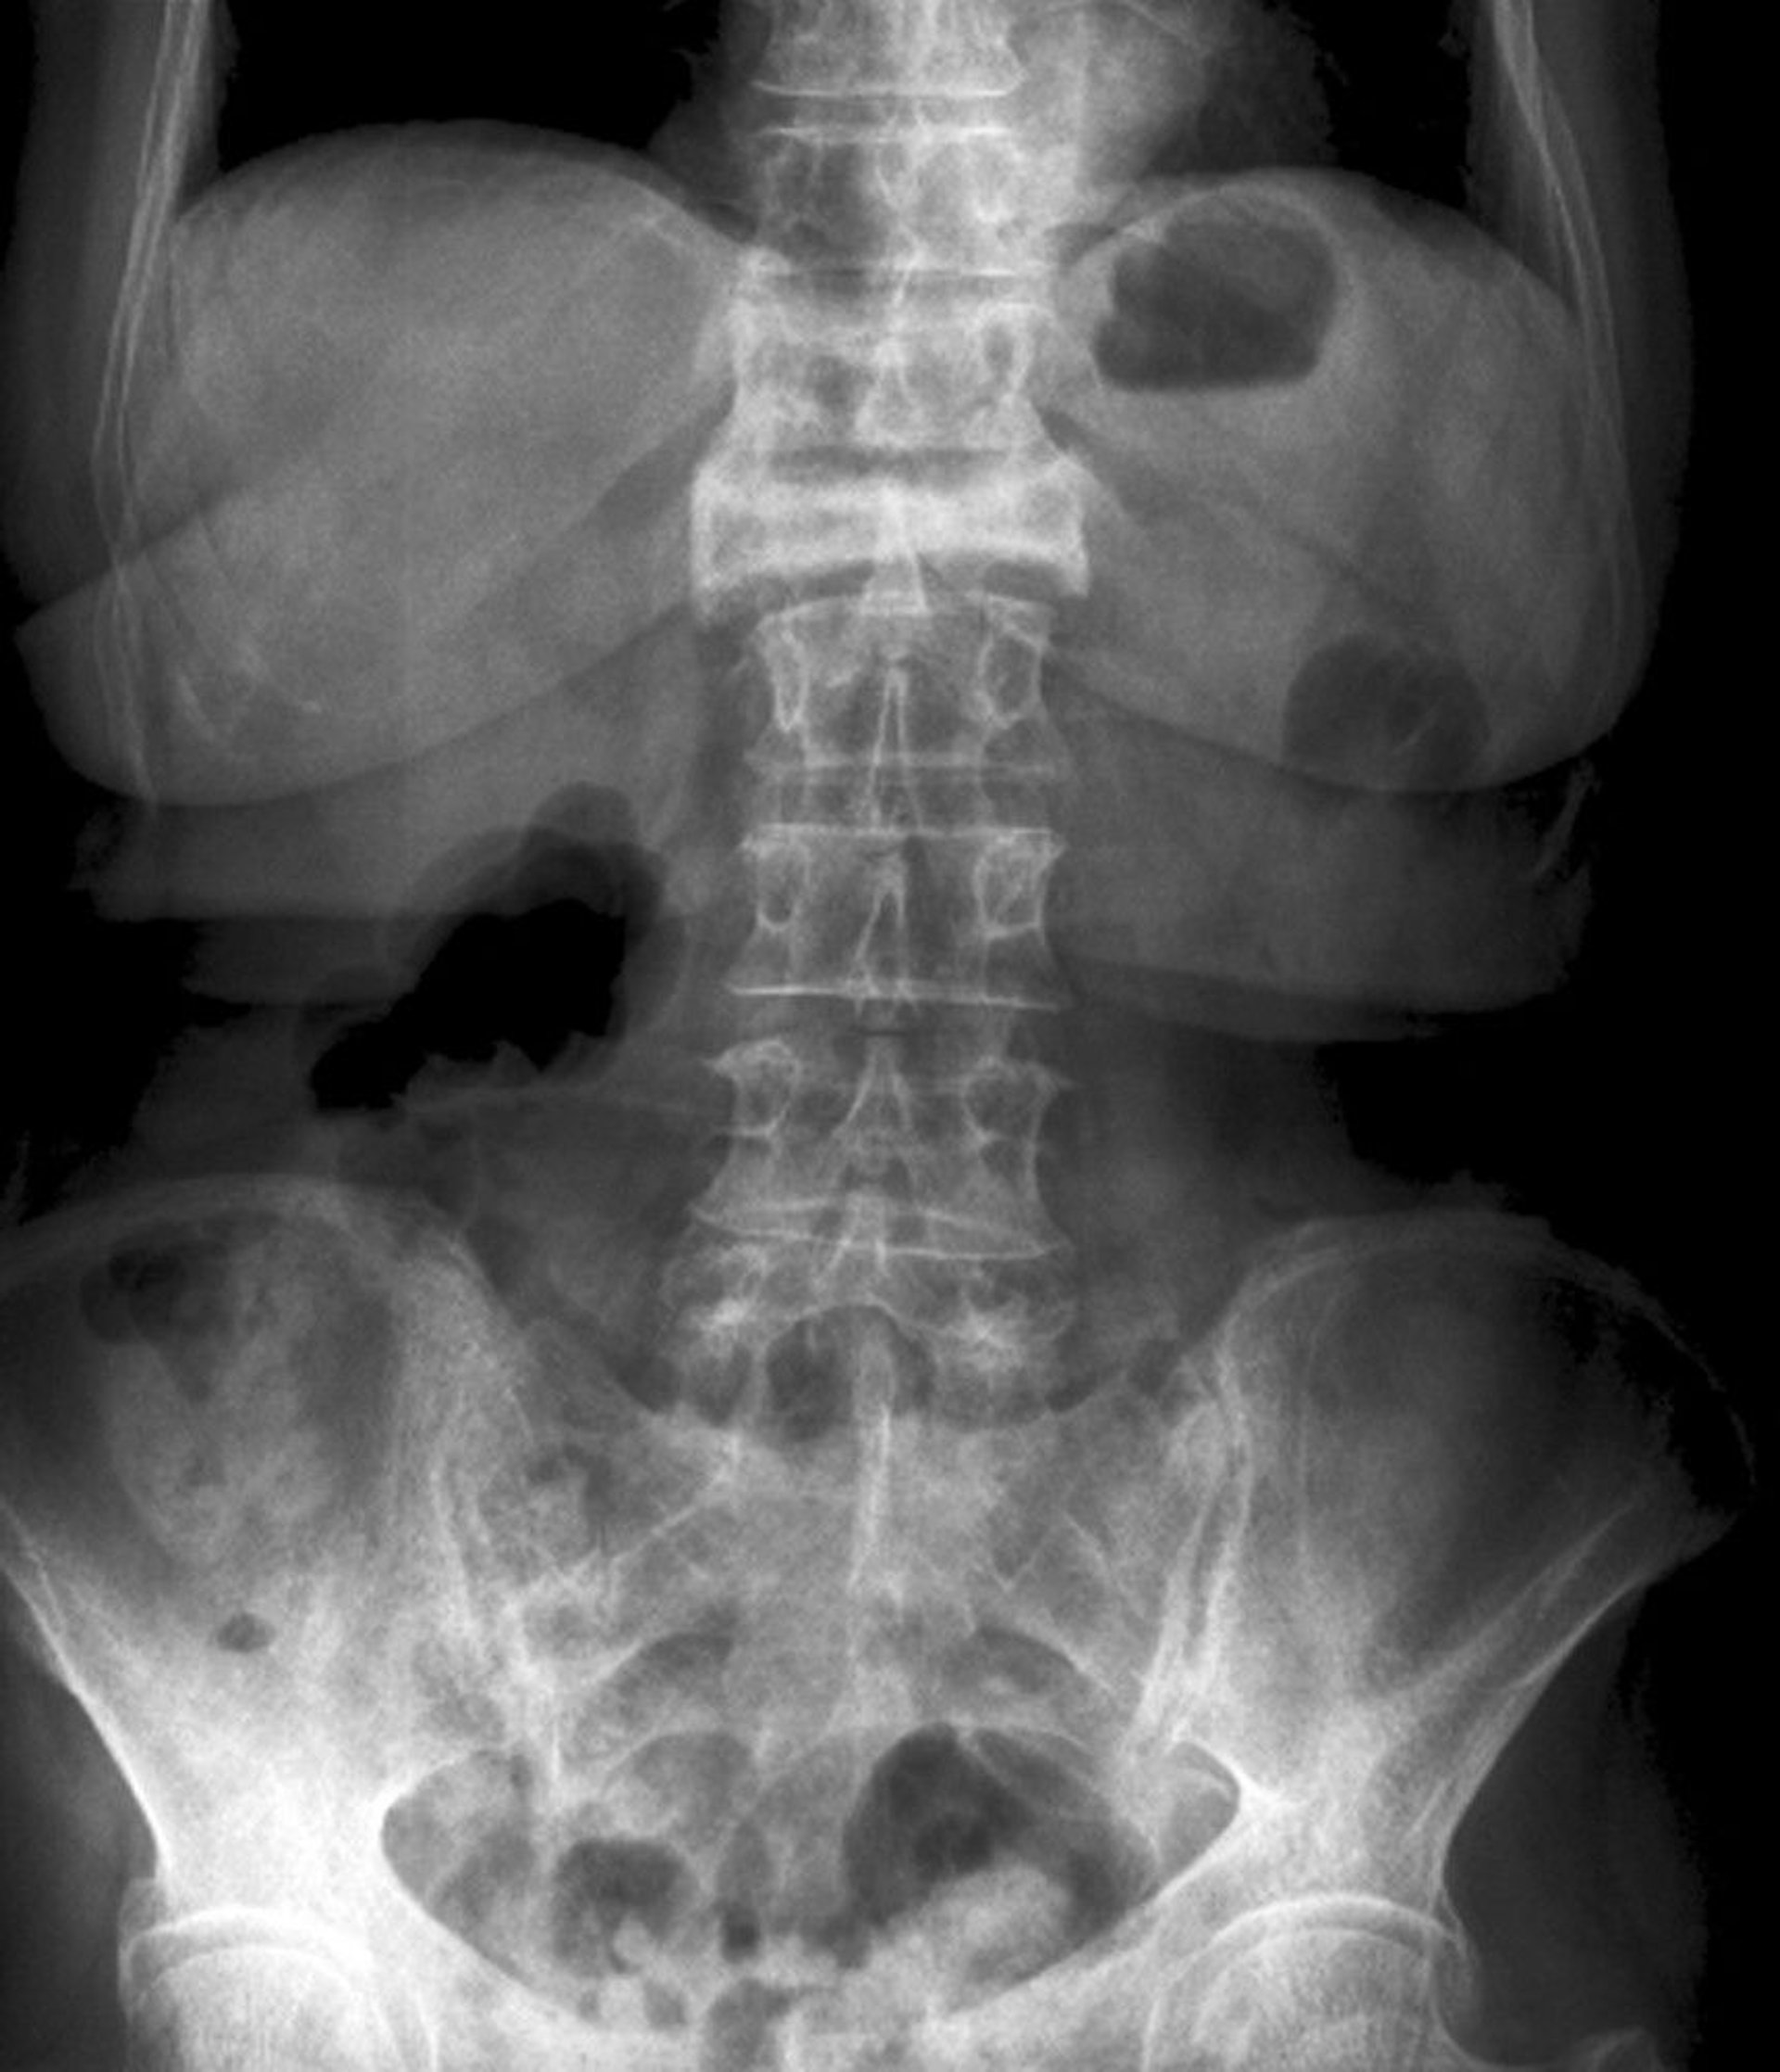

Anteroposterior View of a Severe Compression Fracture

This compression fracture of the 1st lumbar vertebra is visible on the anteroposterior view as a severe loss of height and increased radiodensity.